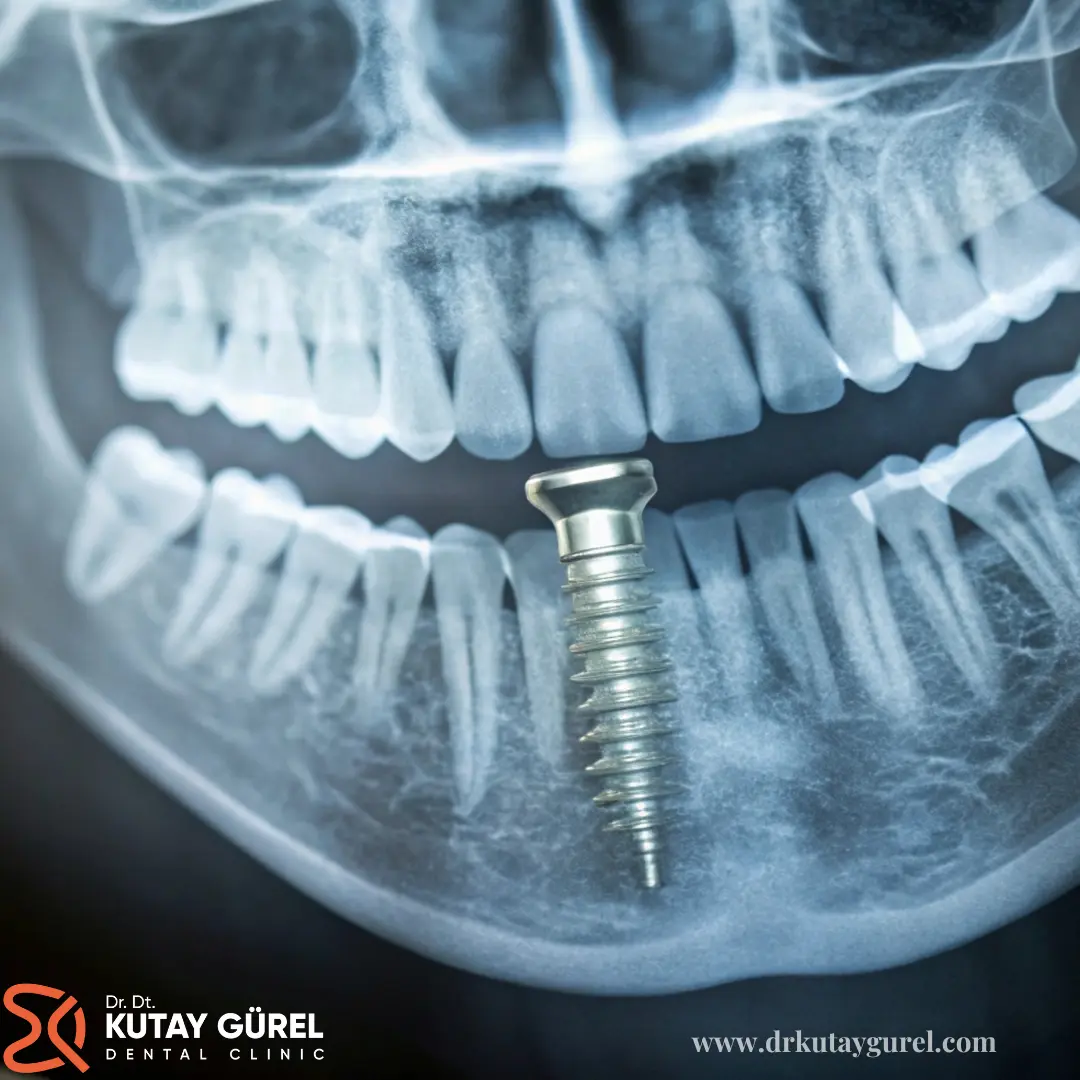

All on 4 implant tedavisi, özellikle dişsiz hastalar arasında yaygın olarak tercih edilen ve başarısı kanıtlanmış bir uygulamadır. Bu tekniğe göre, her bir eksik diş için ayrı ayrı implant yerine, dört adet implant farklı açılarda yerleştirilir ve üzerlerine tüm dişler bir arada takılır.

• Dental implant yerleştirme: Doğru açı ve konumda, çene kemiğinin anatomik yapısına uygun şekilde 4 adet dental implant yerleştirilir. Ön bölümdeki implantlar 90 derece, arka bölümdeki implantlar ise 45 derece açıyla yerleştirilir.

Bu tedavide dört adet implant, alt veya üst çene kemiklerinin uygun bölgelerine açılı olarak yerleştirilir.